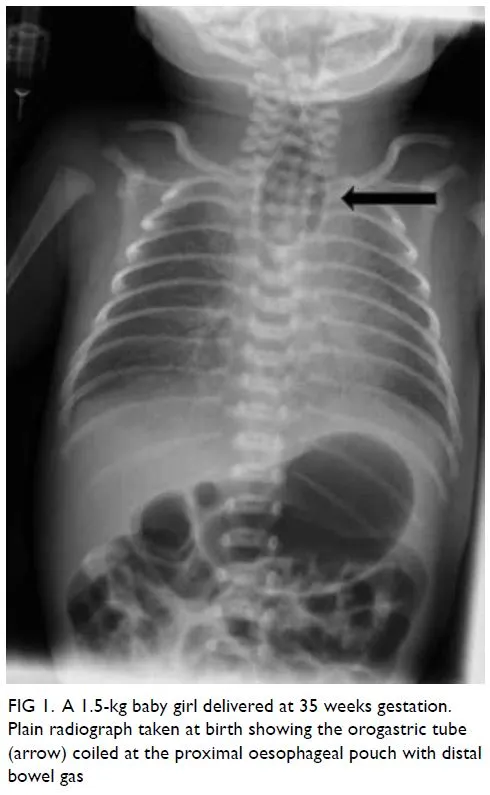

- Confirmation: A chest/abdominal X-ray is the key diagnostic imaging study.

- Shows: Coiled NG tube in the blind esophageal pouch.

- Differentiates: The pattern of bowel gas is critical for classification.

⭐ A gas-filled stomach confirms a patent distal fistula (Type C), the most common variant. A gasless abdomen indicates pure atresia (Type A) or a rare variant without a distal connection.